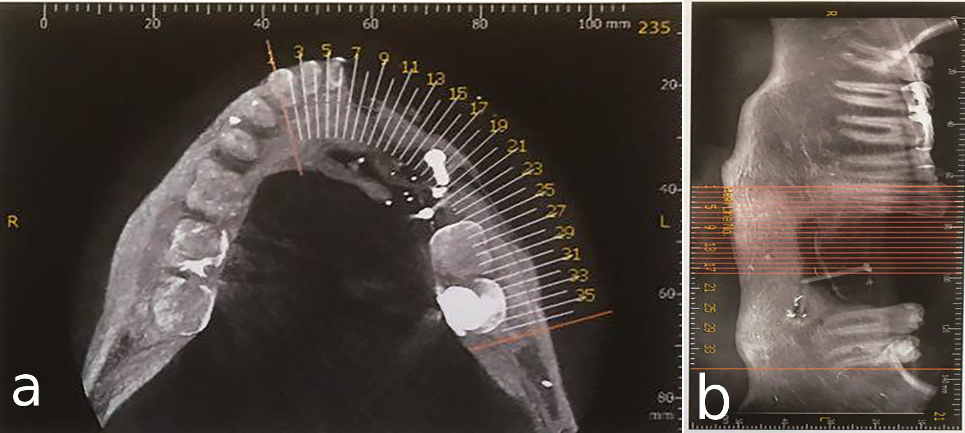

A 30-year-old partially edentulous patient was referred to the Implant Department of Tehran University, School of Dentistry, for prosthetic reconstruction (Figure 1, a and b). The patient had lost 6 teeth due to the trauma of a gunshot. Since the accident had occurred several years prevoiusly and the patient had undergone cosmetic plastic surgery, only a skin scar remained in his lower face. Three implants (Implantium, Dentium, Seoul, South Korea) were placed on the left side of the mandible (Figure 2, a and b). Regarding the increased interocclusal space and improper implant alignment, it was decided to use hybrid screw-retained and cement-retained implant (Toronto) prosthesis.

a) Occlusal view of mandibular arch with three implants. b) Panoramic view of implants placed in defective bone in the left mandible.